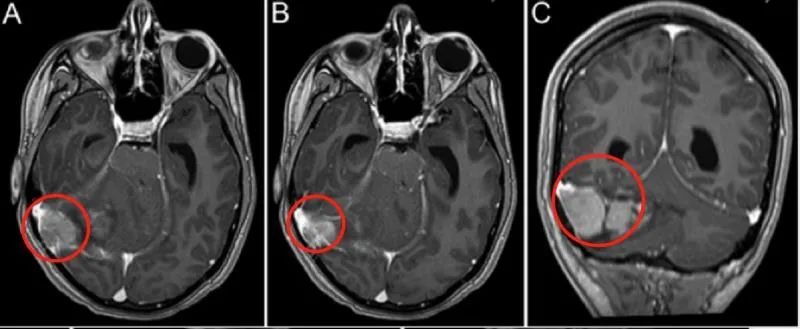

孩子病情耽误不得!父母立刻带着Anita来到加拿大多伦多大学Sickkids医院。核磁扫描结果显示,Anita右侧小脑半球存在 5.6×5.0×3.4 cm的高信号巨大占位,且肿瘤已经压迫第四脑室,伴发梗阻性脑积水。

术后MRI显示Anita的右侧横窦内小脑实质部分全部切除,有少量强化肿瘤(< 1.5c㎡)。术后临床检查显示脑神经正常,无明显运动或感觉功能障碍,轻度舒张功能障碍,轻度躯干共济失调,术后半年症状明显好转。随访 8 年,孩子无神经功能缺损,无肿瘤复发。一次手术,让Anita父母不再提心吊胆,而孩子的未来也缓慢展开……